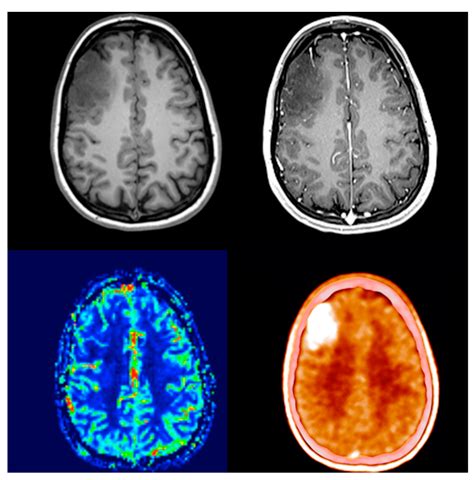

When it comes to modern medical diagnostics, Ct Pet Imaging stands at the forefront of precision medicine. By combining the structural detail of a Computed Tomography (CT) scan with the metabolic insights provided by Positron Emission Tomography (PET), this hybrid technology offers clinicians an unparalleled view of the human body. This dual-modality approach allows medical professionals to identify diseases at their earliest stages, monitor treatment effectiveness, and plan complex procedures with pinpoint accuracy. As healthcare continues to shift toward personalized care, understanding the mechanics and benefits of this advanced diagnostic tool is essential for patients and practitioners alike.

At its core, Ct Pet Imaging is a sophisticated fusion of two distinct imaging technologies. To appreciate how this works, it is important to distinguish the unique contributions of both components:

• PET (Positron Emission Tomography): This functional scan uses a small amount of radioactive tracer to highlight metabolic activity in cells. It is particularly adept at identifying areas with high glucose consumption, which is a hallmark of cancerous tissues.

• CT (Computed Tomography): This structural scan uses X-rays to create detailed, cross-sectional images of the body’s anatomy, bones, and organs.

When these two scans are fused into a single image, the result is a high-definition map that shows exactly where a metabolic abnormality is located in relation to the surrounding anatomy. This eliminates the guesswork often associated with viewing functional and structural data separately.